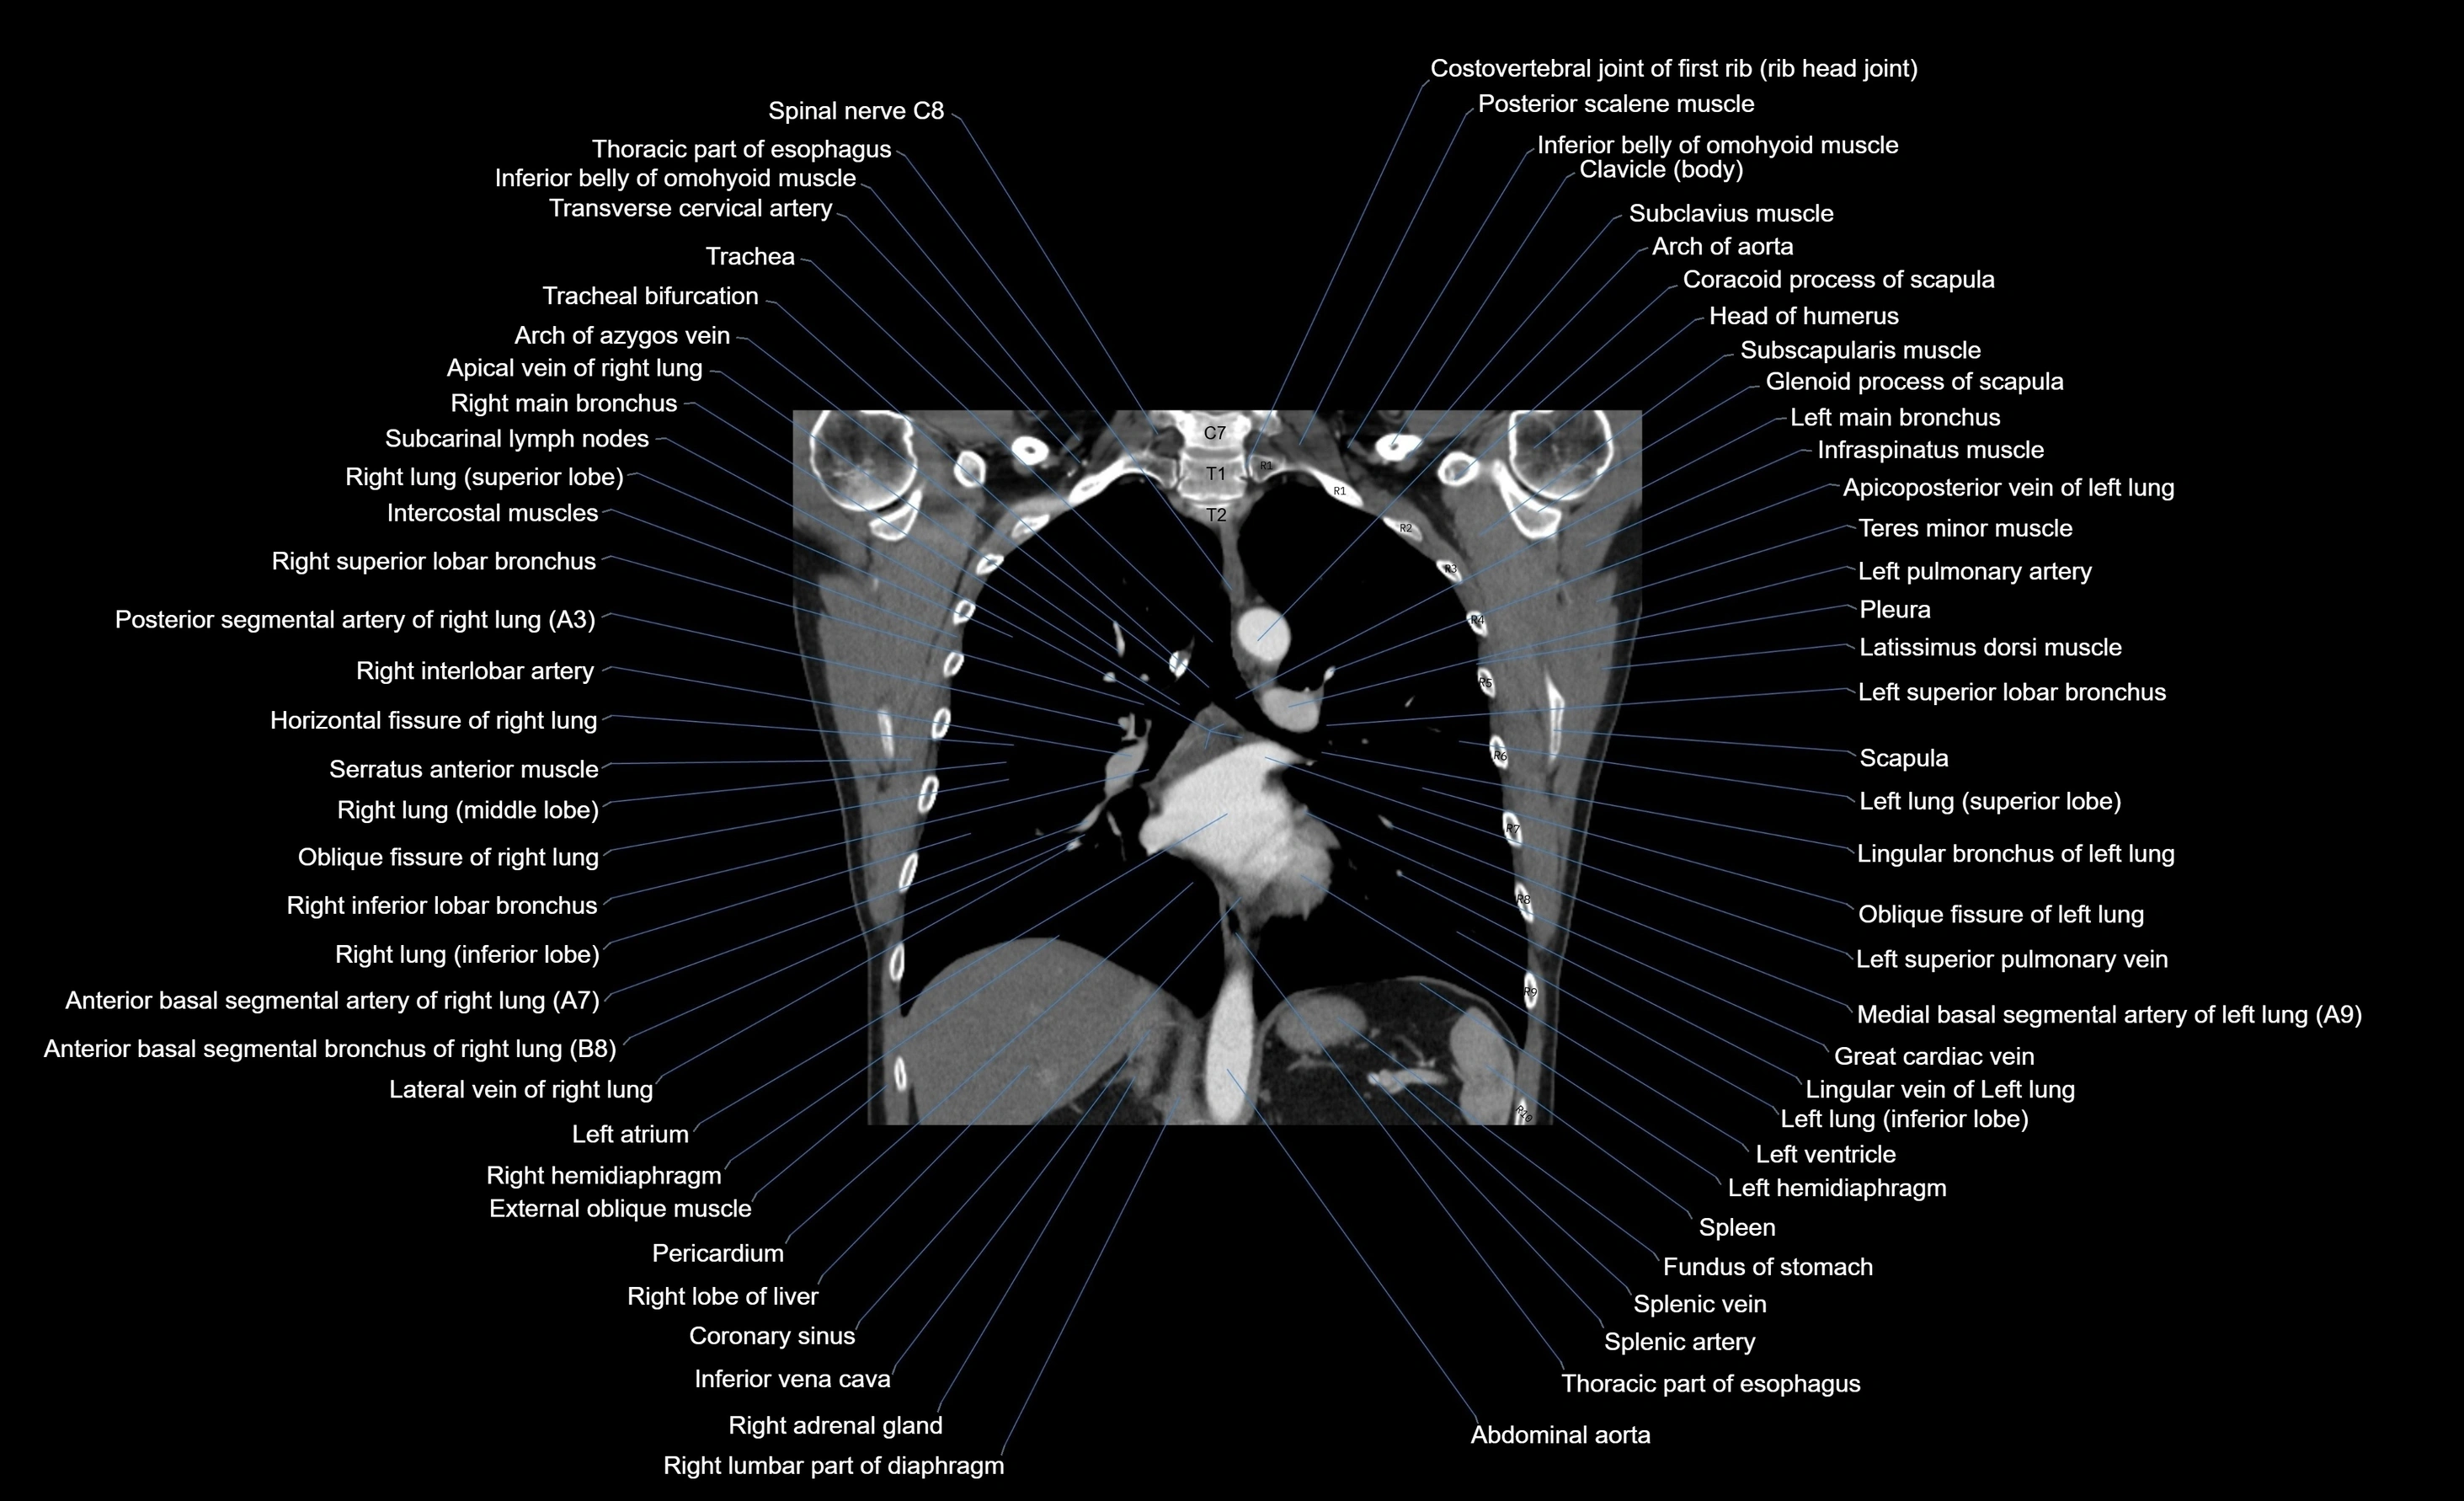

CT images